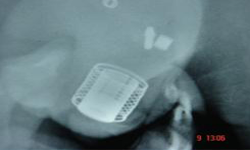

Urethra Exposed Artificial Urinary Sphincter

Device Implanted Device in Place